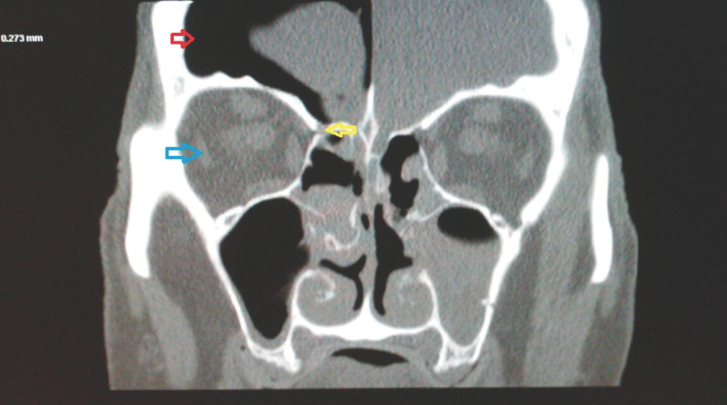

An 18-year-old male without significant past medical history presented with 2-day history of swelling of the forehead located above the right eye.